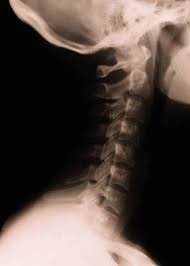

A sample of tissue may be removed to look for the presence of cancerous cells. Some of its most common symptoms include a persistent sore throat and/or cough, difficulty swallowing, hoarseness, ear pain and a neck mass. It can start like a small irregular ulcer with whitish/ redish color. Many people mistake throat cancer with cold or sore throat. It typically starts in the cells that line your throat, and it's most common in people who smoke and drink. A cancerous (malignant) tumour starts from one cell behaving abnormally. Thyroid cancer is a rare type of cancer that affects the thyroid gland, a small gland at the base of the neck that produces hormones. These bacteria do not cause meningitis while in the throat and nose, but getting into the blood, cerebrospinal fluid and soft tissue of the brain, provoke inflammation. Cancer can develop in almost any tissue or organ of the body such as the throat, lung, colon, breast, skin, bones or nerve tissue. Even if it did hurt, you figured it was just a canker sore. Why does the back of my throat feel swollen? Roswell park brings together a team of highly experienced specialists who will review your case to come up with the very. A lump on the tongue :

What does cancer look like in the throat? Why does the back of my throat feel swollen? This is a question every cancer patient has asked about their own illness; It is a growth, swel: What throat cancer look like. What does a cancer lump feel like on a dog? Here are some oral (mouth) cancer pictures so you can. A cancerous (malignant) tumour starts from one cell behaving abnormally. These are benign, meaning not cancerous. Symptoms predominantly include a sore that does not heal or a change in the voice. In later stage it may grow out irregular, often still ulcer like, sometimes bulky. What causes throat (laryngeal) cancer? Though most throat cancers involve the same types of cells, specific terms are used to differentiate the part of the throat where cancer originated.